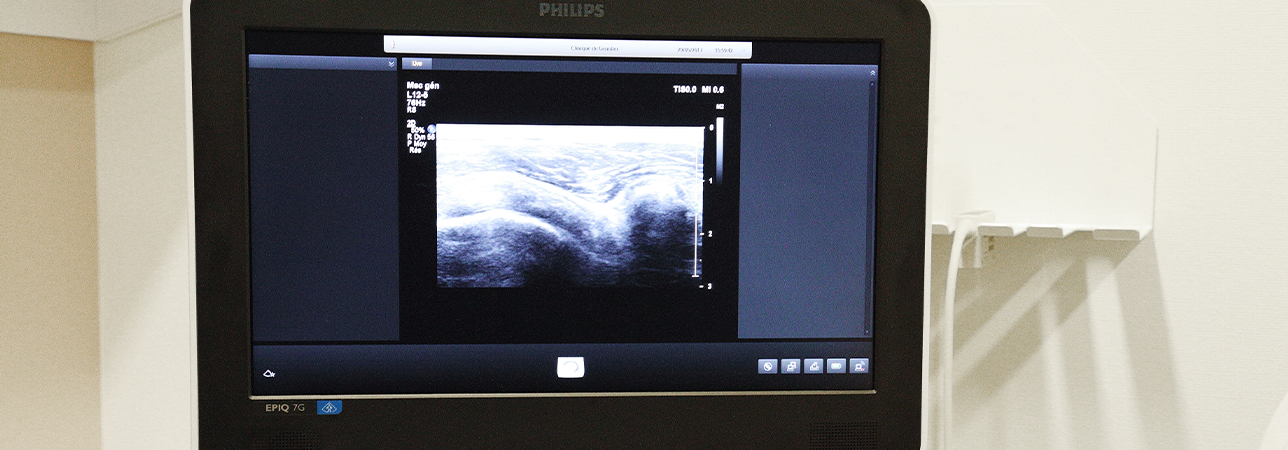

Technisch gesehen handelt es sich um einen Ultraschallstrahl, dessen Frequenz an das zu untersuchende Organ angepasst ist und der sich mehr oder weniger nach den anatomischen Strukturen richtet. Dadurch kann ein Bild des betreffenden Organs erzeugt werden, das direkt auf dem Bildschirm des Gerätes zur dynamischen und unmittelbaren Beurteilung angezeigt wird.

Zu Beginn der Untersuchung trägt der Radiologe auf der Haut über dem zu untersuchenden Bereich ein Gel auf. Dies verhindert, dass zwischen der Sonde und der Haut Luft verbleibt, die eine Übertragung des Ultraschalls verhindert. Die Untersuchung dauert je nach Körperregion 15 bis 30 Minuten.